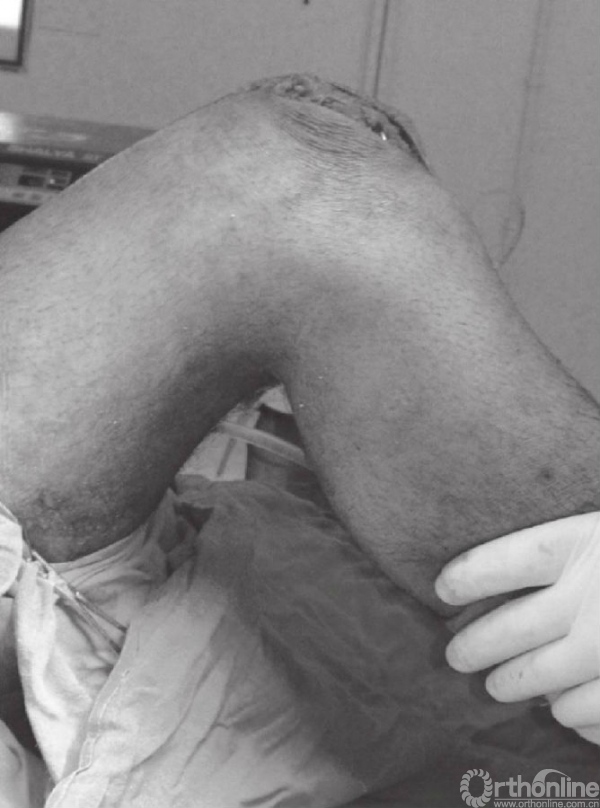

图19 屈膝90°,评估内固定的稳定性

最后,松开止血带,进一步止血。用生理盐水冲洗伤口,可放置引流。采用20号薇乔缝线连续缝合髌前囊。皮下层可采用反向方式缝合,并用尼龙/聚丙烯/金属短钉闭合伤口。伤口包扎于膝盖水平以上,并在膝关节伸展位支具固定。